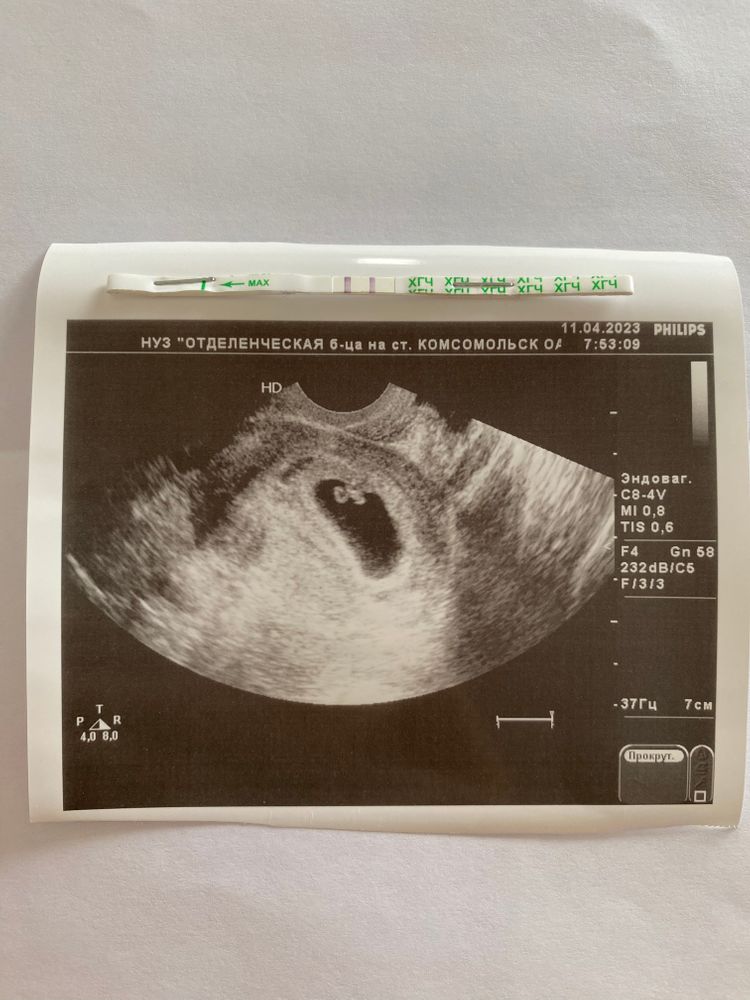

Тоже вчера была у врача в 6нед 4дн. Так мило видеть на экране) Изображение

УЗИ 6 недель и 4 дня